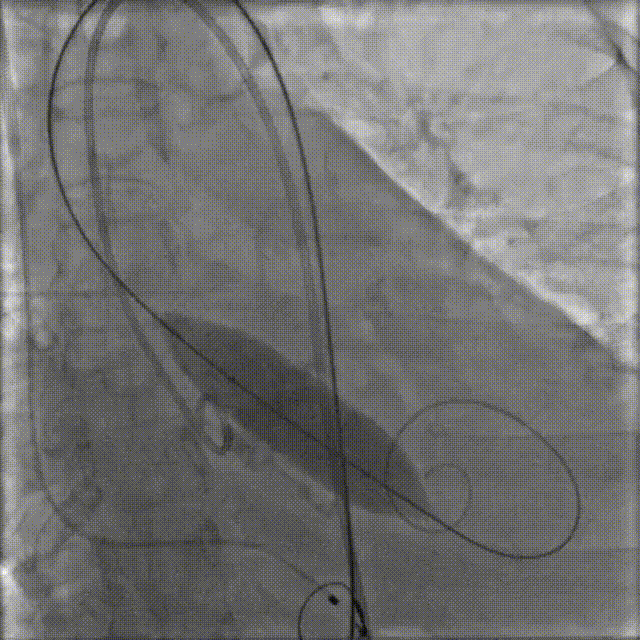

4.VitaFlow liberty™ TAV24瓣膜系统1:1等量精准释放

猪尾巴在无冠窦窦底定位,缓慢释放瓣膜,多次造影评估,实时观察冠脉显影情况.

释放到后1/3,多体位造影评估冠脉及植入深度

5.释放完成

瓣膜释放后造影提示冠脉⽆遮挡

最终瓣膜植入深度可,形态佳,⽆瓣周漏